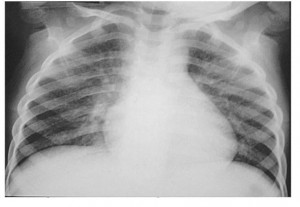

Một trẻ 4 tuổi vào viện vì uống nhầm dầu hỏa giờ thứ 1. Trẻ sau khi ngủ dậy, thấy khát nước đã uống dầu hỏa (không rõ số lượng) đựng trong chai Lavie. Sau đó trẻ ho sặc sụa, mẹ trẻ thấy vậy đã móc họng gây nôn khiến trẻ ho sặc nhiều hơn. Sau khi chụp X- quang phổi, bác sĩ nhận định đây là tình trạng Viêm phổi hít do sặc dầu hỏa. Trẻ có chỉ định dùng kháng sinh, mặc dù lâm sàng trẻ chưa có biểu hiện gì đặc biệt. 48 giờ sau, X- quang phổi của trẻ cho thấy tổn thương phổi tăng lên, trẻ bắt đầu xuất hiện ho húng hắng. Sau 6 ngày điều trị, tổn thương phổi trên X- quang giảm ít, trẻ bắt đầu ho nhiều hơn, có sốt. Điều đó cho thấy tổn thương viêm phổi hít do sặc dầu hỏa rất nặng nề, nguy cơ bội nhiễm cao và cần điều trị kéo dài.